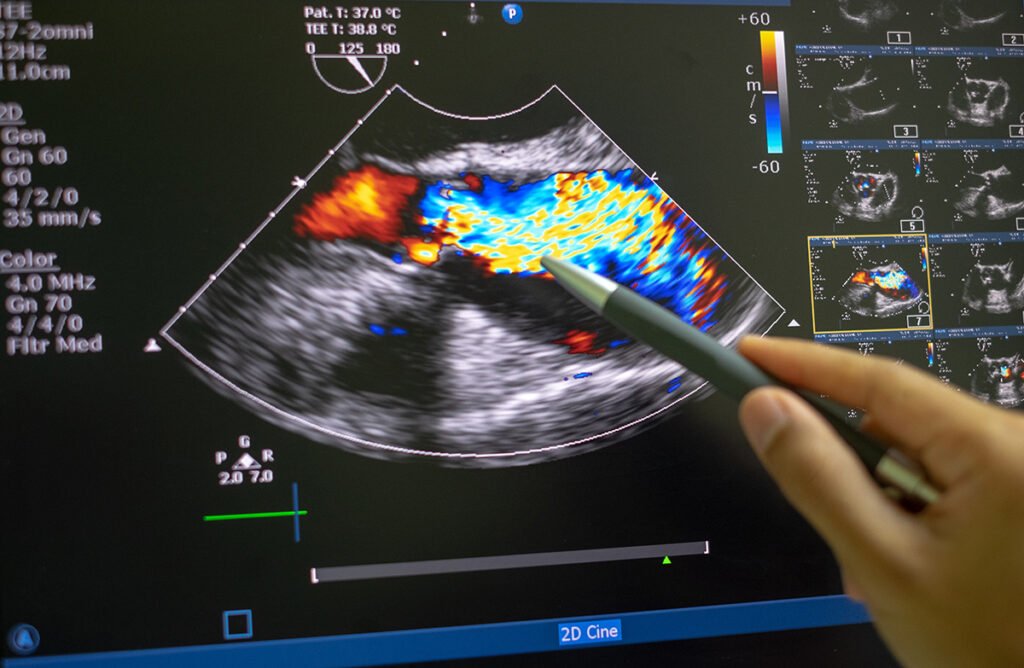

An echocardiogram uses ultrasound to assess the heart’s structure and function. It evaluates heart chambers, valves, pumping efficiency, and overall performance.

This test helps detect conditions such as valve disease, weakened heart muscle, or abnormal heart motion.